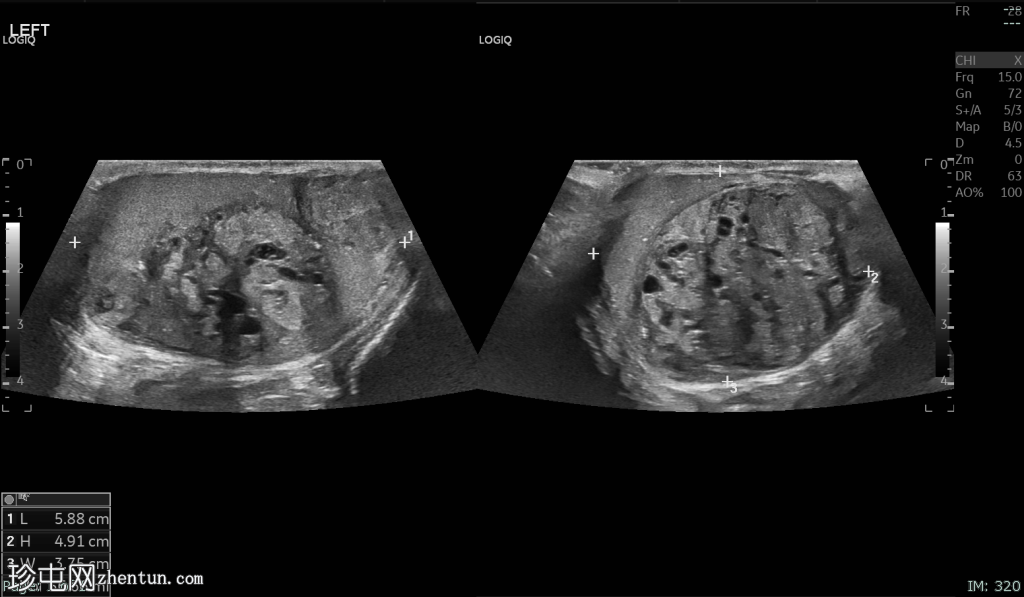

超声检查

左侧睾丸肿大,体积约56 mL,可见弥漫性微结石,以及三个内部等回声病灶,伴囊性变、微钙化和明显血流信号,最大病灶大小约4.8 x 3.2 cm。

未见腹主动脉旁或髂淋巴结肿大。